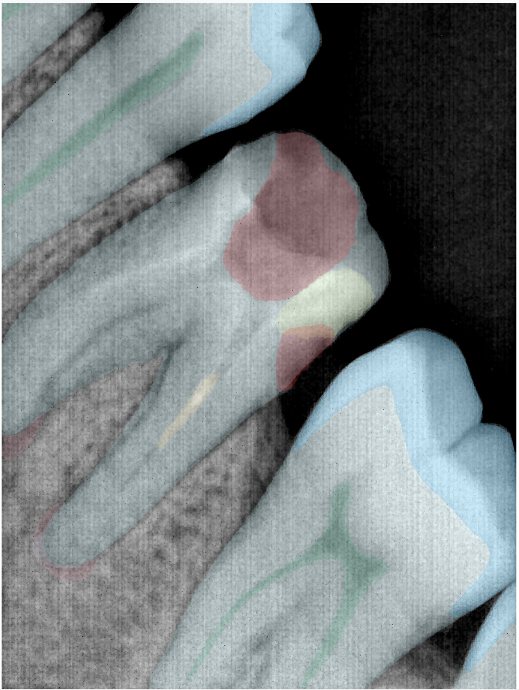

第三版算法分辨率效果比较

| 编号 | 原图 | 第一版 | 第二版 | 第三版 1216x1600 | 第三版 768x1024 | 第三版 1120x1120 |

|---|---|---|---|---|---|---|

| 131315.jpg | ![]() | ![]() | ![]() | ![]() | ![]() | ![]() |

| 131316.jpg | ![]() | ![]() | ![]() | ![]() | ![]() | ![]() |

| 131317.jpg | ![]() | ![]() | ![]() | ![]() | ![]() | ![]() |

| 131318.jpg | ![]() | ![]() | ![]() | ![]() | ![]() | ![]() |

| 131319.jpg | ![]() | ![]() | ![]() | ![]() | ![]() | ![]() |

| 131320.jpg | ![]() | ![]() | ![]() | ![]() | ![]() | ![]() |

| 131321.jpg | ![]() | ![]() | ![]() | ![]() | ![]() | ![]() |

| 131326.jpg | ![]() | ![]() | ![]() | ![]() | ![]() | ![]() |

| 131327.jpg | ![]() | ![]() | ![]() | ![]() | ![]() | ![]() |

| 131328.jpg | ![]() | ![]() | ![]() | ![]() | ![]() | ![]() |

| 131330.jpg | ![]() | ![]() | ![]() | ![]() | ![]() | ![]() |

| 131331.jpg | ![]() | ![]() | ![]() | ![]() | ![]() | ![]() |

| 131332.jpg | ![]() | ![]() | ![]() | ![]() | ![]() | ![]() |

| 131333.jpg | ![]() | ![]() | ![]() | ![]() | ![]() | ![]() |

| 131334.jpg | ![]() | ![]() | ![]() | ![]() | ![]() | ![]() |

| 131336.jpg | ![]() | ![]() | ![]() | ![]() | ![]() | ![]() |

| 131337.jpg | ![]() | ![]() | ![]() | ![]() | ![]() | ![]() |

| 131338.jpg | ![]() | ![]() | ![]() | ![]() | ![]() | ![]() |

| 131339.jpg | ![]() | ![]() | ![]() | ![]() | ![]() | ![]() |

| 131340.jpg | ![]() | ![]() | ![]() | ![]() | ![]() | ![]() |

| 131341.jpg | ![]() | ![]() | ![]() | ![]() | ![]() | ![]() |

| 131342.jpg | ![]() | ![]() | ![]() | ![]() | ![]() | ![]() |

| 131344.jpg | ![]() | ![]() | ![]() | ![]() | ![]() | ![]() |

| 131345.jpg | ![]() | ![]() | ![]() | ![]() | ![]() | ![]() |

| 131346.jpg | ![]() | ![]() | ![]() | ![]() | ![]() | ![]() |

| 131347.jpg | ![]() | ![]() | ![]() | ![]() | ![]() | ![]() |

| 131348.jpg | ![]() | ![]() | ![]() | ![]() | ![]() | ![]() |

| 131349.jpg | ![]() | ![]() | ![]() | ![]() | ![]() | ![]() |

| 131350.jpg | ![]() | ![]() | ![]() | ![]() | ![]() | ![]() |

| 131354.jpg | ![]() | ![]() | ![]() | ![]() | ![]() | ![]() |

| 131355.jpg | ![]() | ![]() | ![]() | ![]() | ![]() | ![]() |

| 131356.jpg | ![]() | ![]() | ![]() | ![]() | ![]() | ![]() |

| 131357.jpg | ![]() | ![]() | ![]() | ![]() | ![]() | ![]() |

| 131360.jpg | ![]() | ![]() | ![]() | ![]() | ![]() | ![]() |

| 131362.jpg | ![]() | ![]() | ![]() | ![]() | ![]() | ![]() |

| 131363.jpg | ![]() | ![]() | ![]() | ![]() | ![]() | ![]() |

| 131364.jpg | ![]() | ![]() | ![]() | ![]() | ![]() | ![]() |

| 131365.jpg | ![]() | ![]() | ![]() | ![]() | ![]() | ![]() |